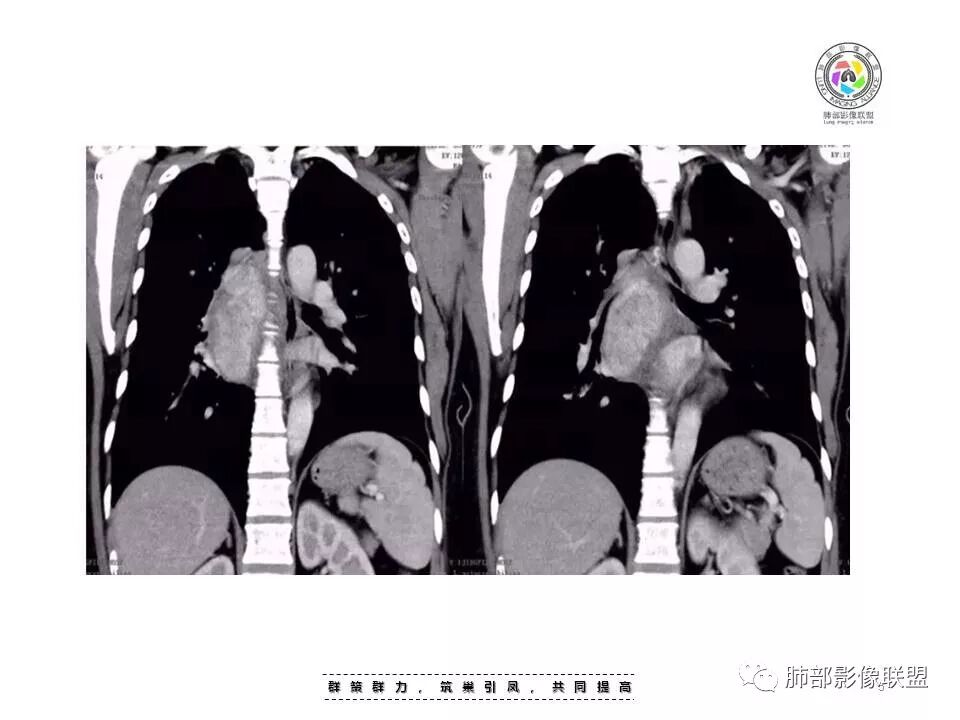

女,35岁 因“体检发现纵隔占位”入院,患者3天前体检发现肺部异常,外院胸部CT示右后纵隔占位,纵隔淋巴结影,未诉明显不适,无心慌胸闷,无头晕头痛,无恶心呕吐,无腹胀腹痛,无吞咽困难。

后纵膈,脊柱旁

明显血管样强化

按理:CD、付节瘤

CD:附近、内部血管多;但是这一点付节瘤也是

CD:附近晕征、附近多发子灶,这一点付节瘤不具备

结果:巨大淋巴结增生病(Castleman,s, disease,CD)

(1)可发生于淋巴结存在的任何部位,60%-70%发生于胸部纵隔

(3)影像表现上,多发单发的圆形或类圆形软组织密度影;透明血管型在CT增强扫描时早期可显著均匀强化,与大血管强化程度相似,原因在于有较多的供养血管,及病灶的毛细血管异常增生和扩展所致;而浆细胞型强化没有前者明显